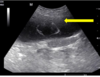

What does this show?

Left – large soft tissue structure. Non contrast; non filtering enlarged L kidney

R – some contrast in ureter and leaving renal pelvis